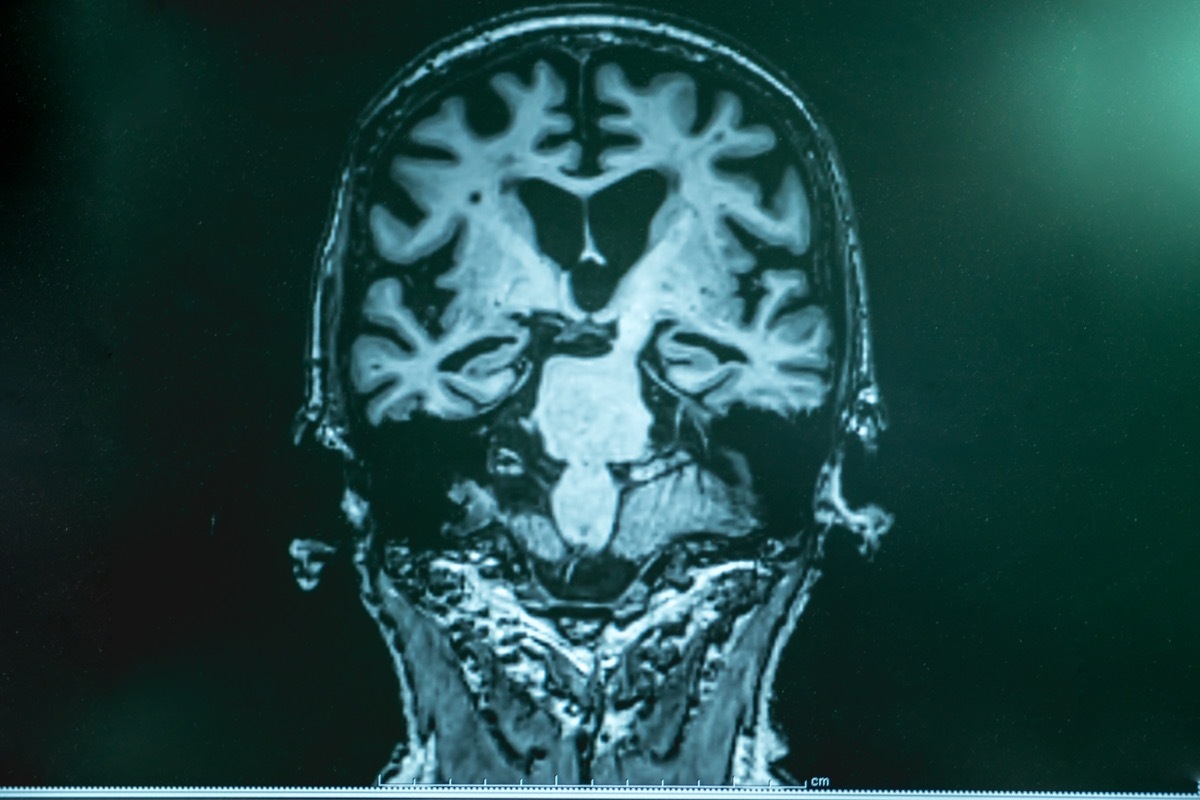

Demenz lässt Ihr Gehirn schrumpfen.

Experten sagen, dass die Gehirne von Menschen mit Demenzatrophie mit einer höheren und schnelleren Geschwindigkeit als gewöhnlich leben. "Es wird angenommen, dass die mit der Alzheimer -Krankheit verbundene Gehirnschrumpfung durch die angesammelte Schädigung von Plaques verursacht wird, die durch eine Art Protein verursacht werden", erklärt Renn. "Es ist jedoch nicht klar, warum diese Proteine fälschen und sich ansammeln - und ob es sich um eine Ursache oder eine Folge der Alzeheimer -Krankheit handelt."

Michael Roizen, MD, Chief Wellness Officer Emeritus in der Cleveland Clinic,Autor vonDer große Neustart des Altersund Gründer vonDer große Neustart des Alters Fügt hinzu: "Stress ist eine Hauptursache für das Gehirnschrumpfung bei normalen Menschen, aber mangelnde Verbindungen und mangelnde Verwendung sind Hauptfaktoren."

ZumDiese jüngste Studie, Forscher teilen 107 Teilnehmer mit MCI in zwei Gruppen auf: eines in webbasierten Kreuzworträtseln und eine in kognitiven Videospielen ausgebildet. Nach 78 Wochen zeigte die Kreuzworträtselgruppe eine größere kognitive Verbesserung und weniger Gehirnschrumpfung.